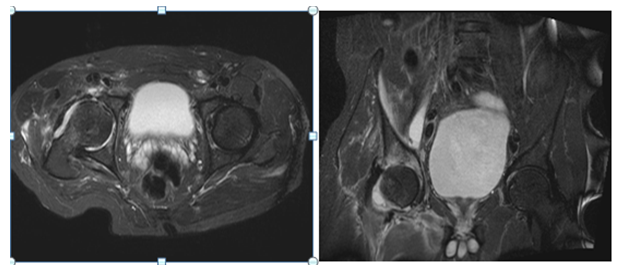

Two stage treatments consisted in an initial surgery through a posterior approach, debridement of inflammatory tissues, neck osteotomy and acetabular reaming adding a temporal non-articulated antibiotic impregnated cement spacer for the resected femoral head. 6 weeks after surgery when intravenous antibiotic treatment was completed and laboratory inflammatory parameters were controlled, a second stage surgery was planified: Conversion to a hybrid arthroplasty for the first case and a non cemented total hip arthroplasty for the second case (Figure 1) (Figure 2).

Figure 1: 60 year old diabetic male patient. A and B Plain X rays showing the narrowing of the hip joint, consequent to a psoas absess. C, D are MRI images showing the acetabular edema and sinovytis associated to psoas edema. E and F postoperative arthroplasty x-ray. Differed anatomy showed chronic inflammation compatible with osteomielitis but no germs were isolated in the cultures. Harris Hip score was 94 at 2 year follow up, infection markers controlled and no complications were reported.